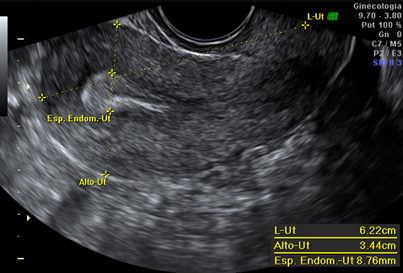

Hospital Universitario Quirónsalud Madrid ofrece la posibilidad de realizar ecografía ginecológica de alta resolución para la caracterización y estudio de patología encontrada durante exploraciones ginecológicas rutinarias, como quistes ováricos, pólipos endometriales, miomas, etc.

El estudio mediante tecnología doppler (que permite el estudio de los vasos sanguíneos y las características de la circulación de la sangre) y tridimensional complementa el estudio con la ecografía de alta resolución, y ofrece la posibilidad de realizar un diagnóstico más exacto de los hallazgos durante la exploración ecográfica.

Ecografía ginecológica de útero.